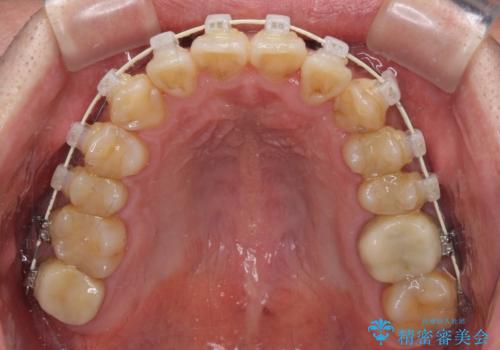

- 虫歯が多く、セラミッククラウンにより虫歯治療を行っている途中で矯正治療をしたいとのことで来院された患者様です。

上顎前歯が舌側に転位しており、なるべく早く楽に矯正したいとのことで、ワイヤー矯正を行うこととしました。

虫歯治療途中の歯は仮歯が装着されていたため、そのまま矯正治療を行い、矯正後に補綴治療を行うこととしました。